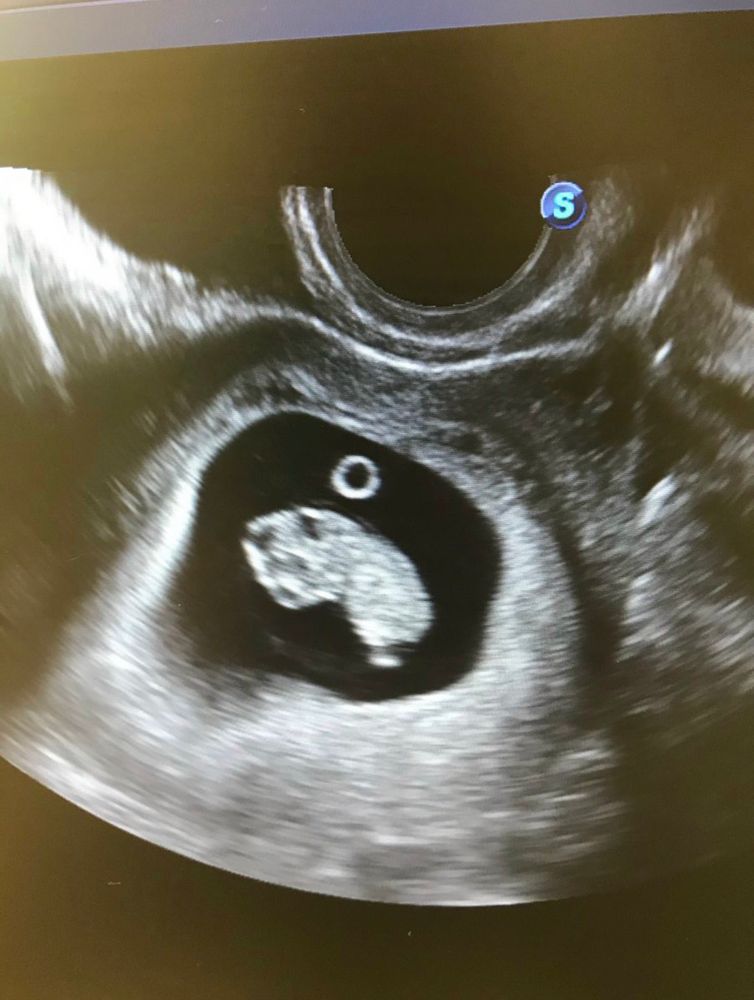

Фотки важных моментов))